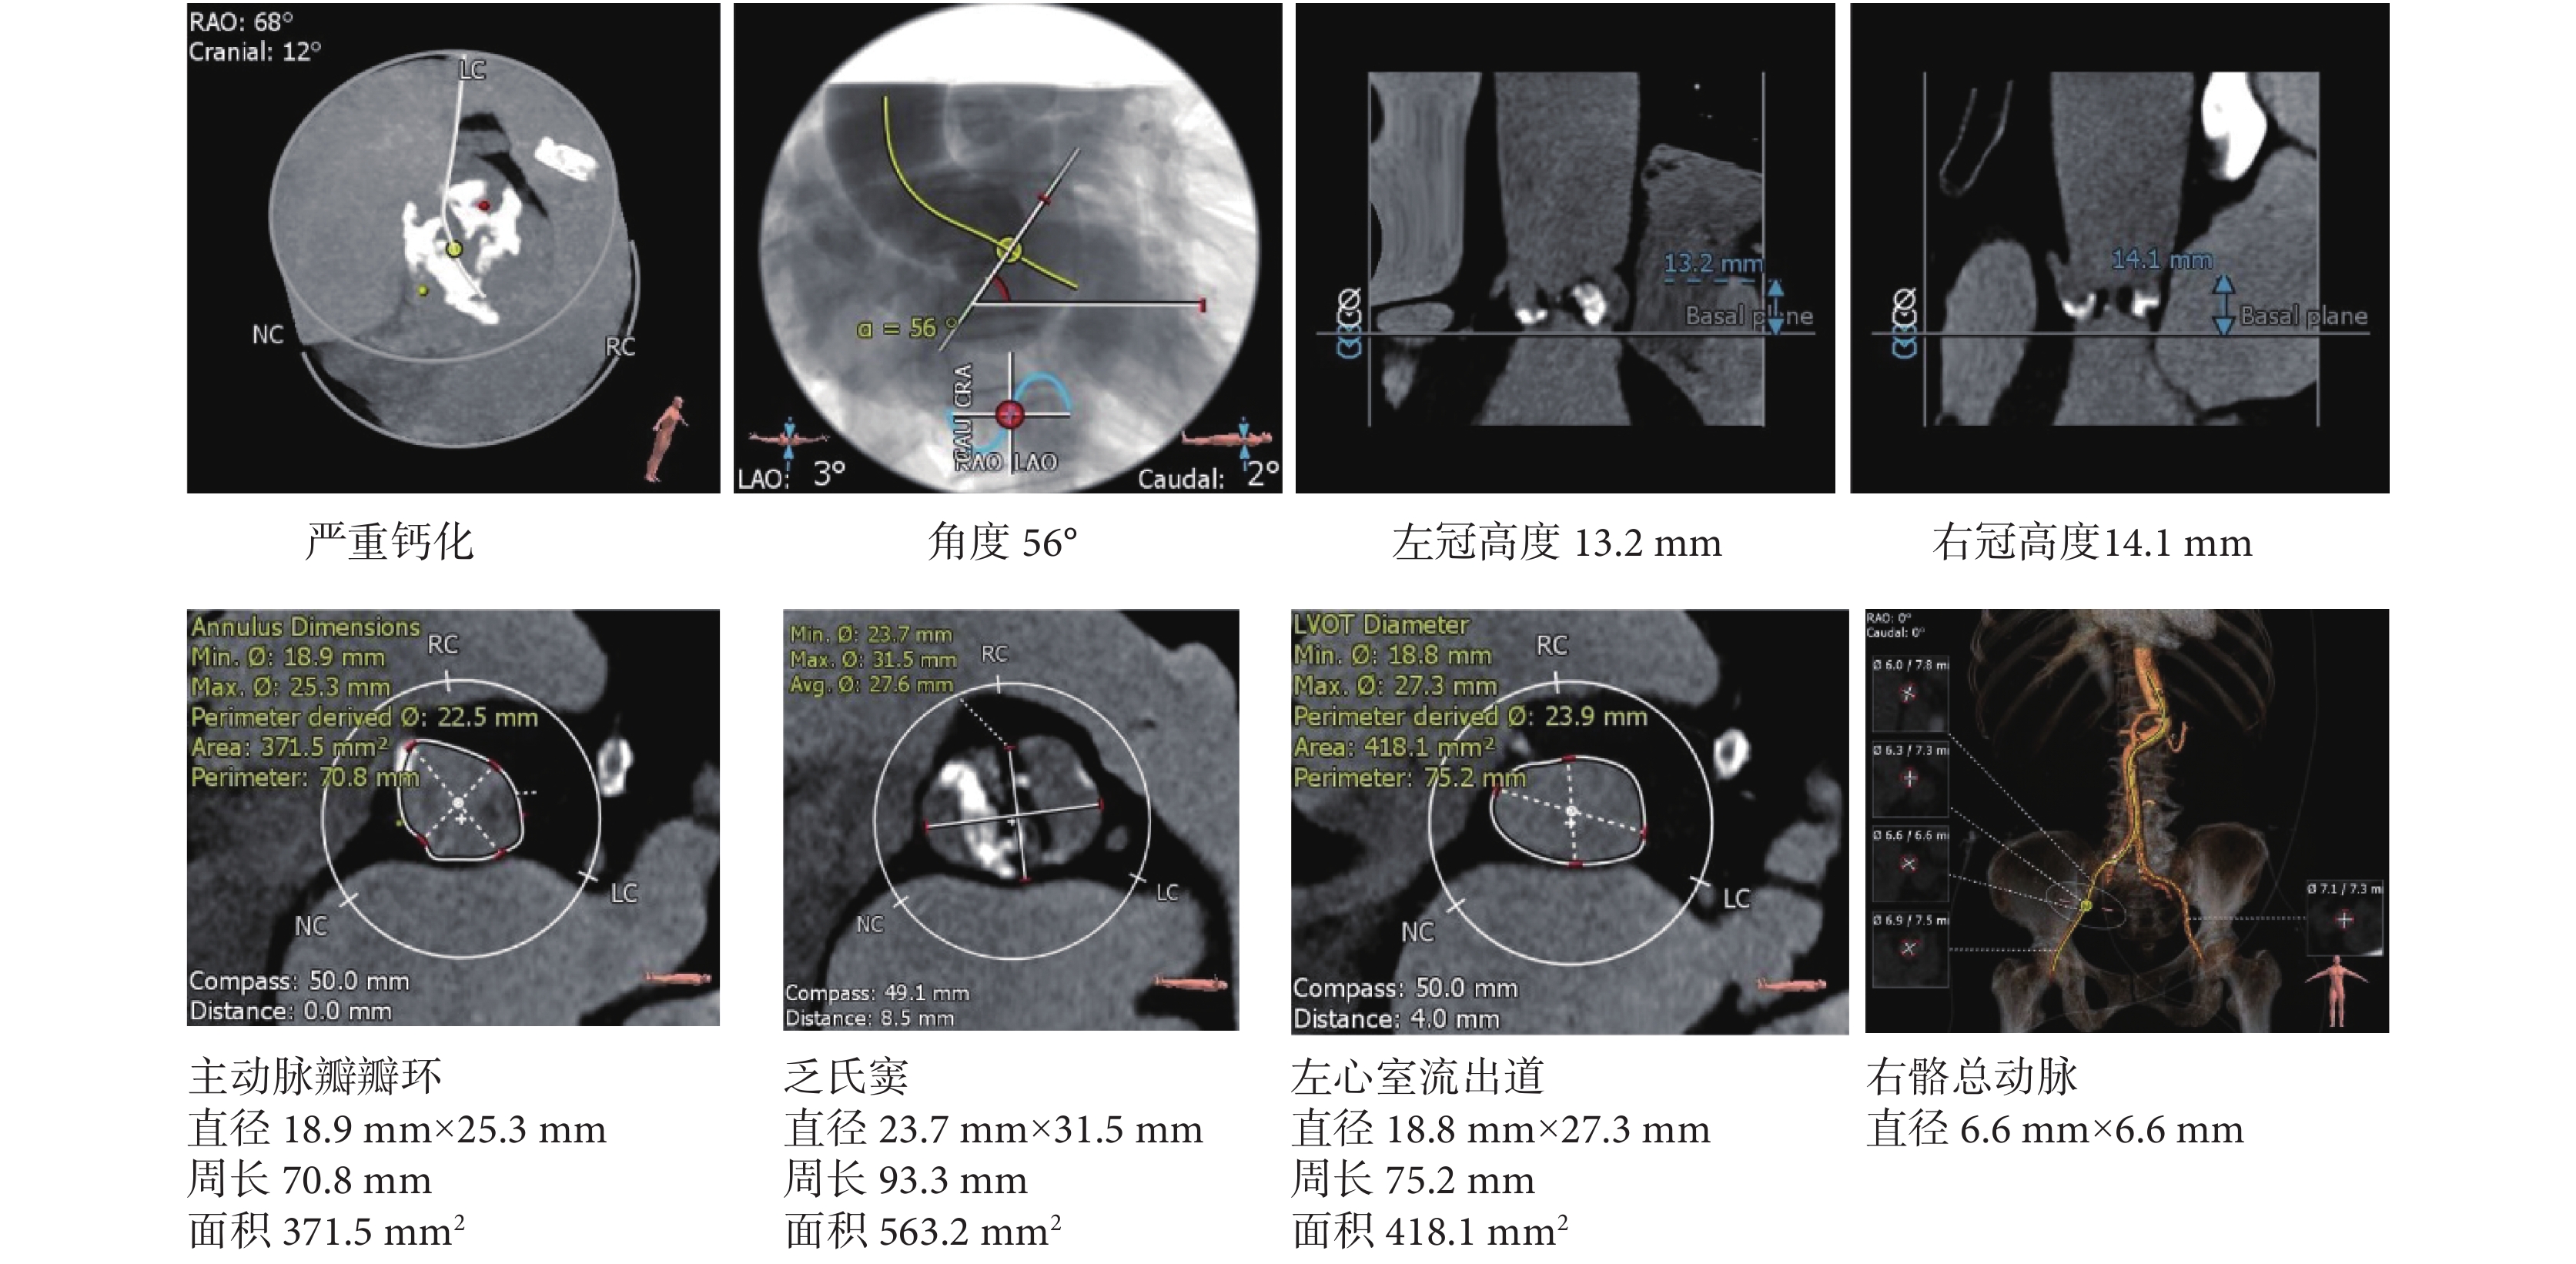

主動脈 CT 血管造影:主動脈瓣重度鈣化;主動脈與左心室夾角 56°;左冠高度 13.2 mm,右冠高度 14.1 mm;主動脈瓣瓣環大小 18.9 mm×25.3 mm,周徑 70.8 mm,面積 371.5 mm2;乏氏竇大小 23.7 mm×31.5 mm,周徑 93.3 mm,面積 563.2 mm2;左心室流出道大小 18.8 mm×27.3 mm,周徑 75.2 mm,面積 418.1 mm2;右髂總動脈直徑 6.6 mm。見圖 1。